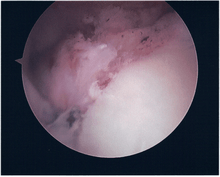

Surgical treatment of SLAP tears has become more common in recent years. The success rate for repairing isolated SLAP tears is reported between 74-94%.[8] While surgery can be performed as a traditional open procedure, an arthroscopic technique[9] is currently favored being less intrusive with low chance of iatrogenic infection.[10]

Procedure

Following inspection and determination of the extent of injury, the basic labrum repair is as follows.

- The glenoid and labrum are roughened to increase contact surface area and promote re-growth.

- Locations for the bone anchors are selected based on number and severity of tear. A severe tear involving both SLAP and Bankart lesions may require seven anchors. Simple tears may only require one.

- The glenoid is drilled for the anchor implantation.

- Anchors are inserted in the glenoid.

- The suture component of the implant is tied through the labrum and knotted such that the labrum is in tight contact with the glenoid surface.